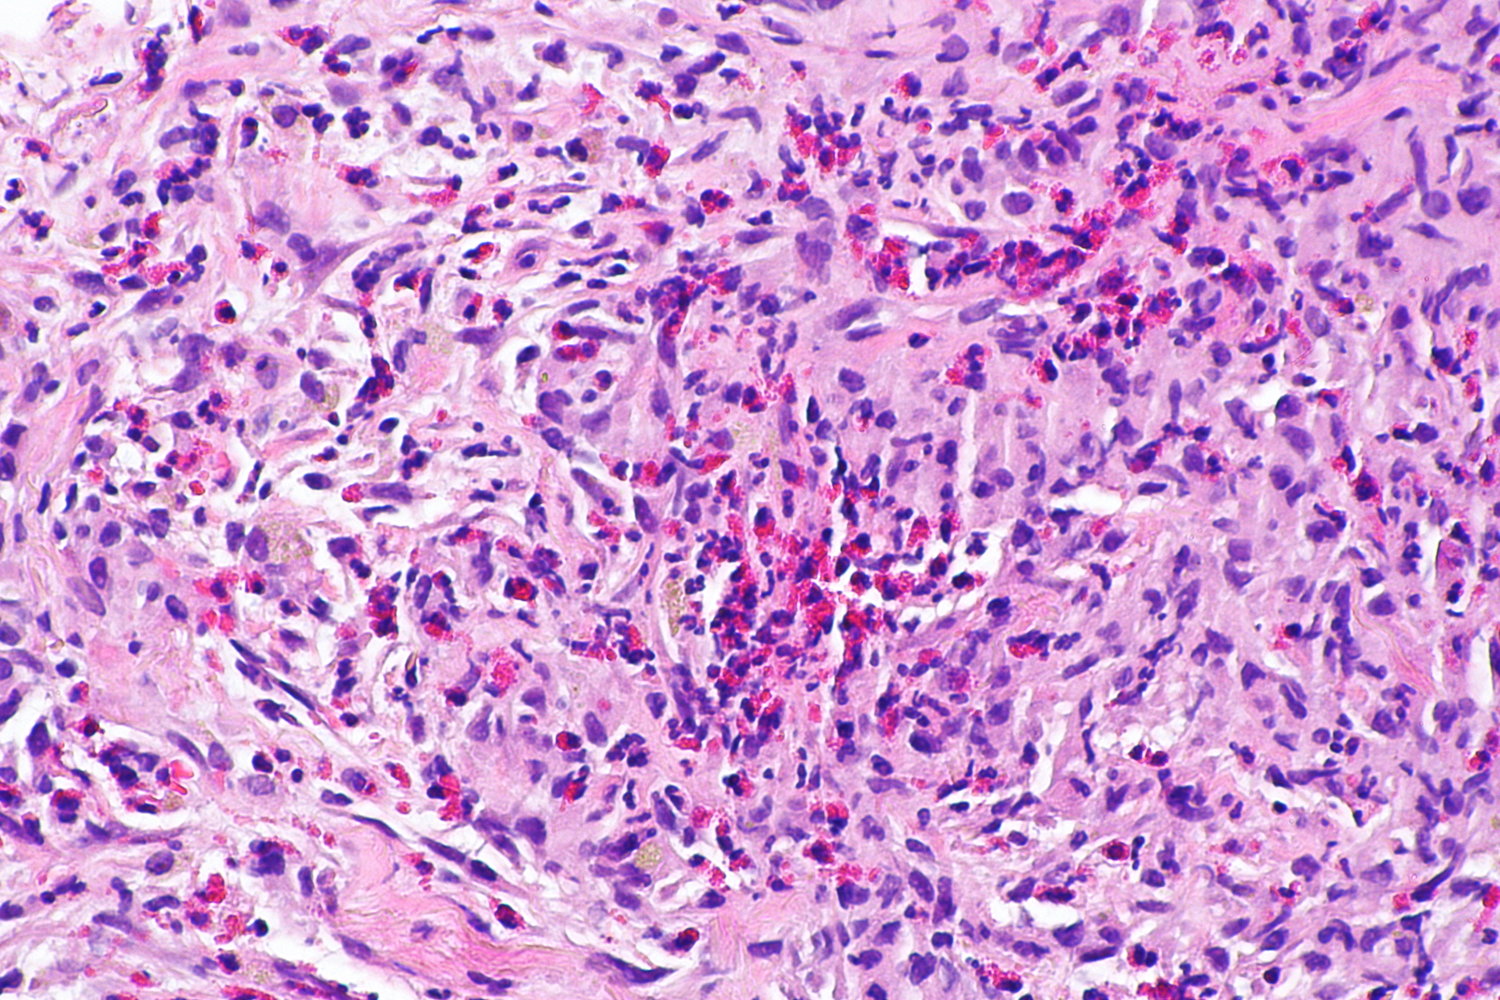

• Histopathology

• Mononuclear, RANKL-expressing cells (neoplastic)

• Multinucleated giant cells (are reactive and resemble osteoclasts)